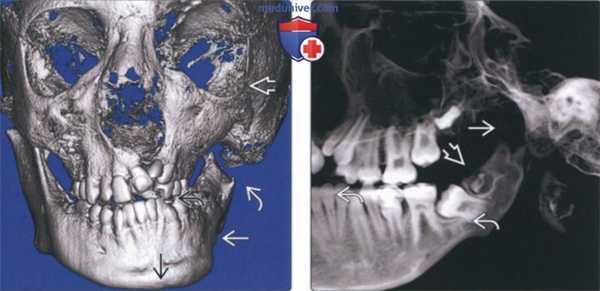

(Слева) На фотографии девочки (анфас) 13 лет определяется асимметрия лица, связанная с ПРМ правого мыщелка. Мягкотканная срединная линия подбородка смещена влево. Угол рта справа приподнят.

(Справа) На КЛКТ (трехмерная реконструкция, вид спереди) у этой же пациентки определяется асимметрия лица. Костная срединная линия нижней челюсти отклонена вправо, окклюзионная плоскость справа приподнята, как и правый угол нижней челюсти. (Слева) На панорамной реформатированной КЛКТ у этой же пациентки определяется недоразвитие нижней челюсти справа. Правая ветвь короче, чем левая. Правый венечный отросток удлинен, правый мыщелковый отросток укорочен.

(Справа) На панорамной реформатированной КЛКТ у этой же пациентки нижняя челюсть слева сформирована нормально. Вертикальный размер тела нижней челюсти слева больше, чем справа. Антегониальная вырезка неглубокая. (Слева) На корональной косой и парасагиттальной реконструкциях (КЛКТ) правого ВНЧС у этой же пациентки определяются признаки стабильной ПРМ. Верхняя поверхность мыщелка уплощена и покрыта кортикальной пластинкой. Обратите внимание на глубокое вдавление в заднем крае ветви и наиболее выдающуюся точку заднего контура, находящуюся возле верхней поверхности.

(Справа) На КЛКТ левого ВНЧС у этой же пациентки визуализируется нормально сформированный мыщелок с мелким дефектом кортикальной пластинки со стороны верхней поверхности, наличие которого означает раннюю активную стадию ПРМ.